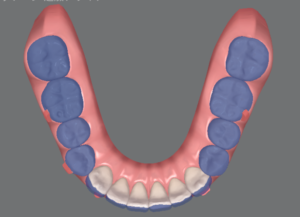

実際にオーバーコレクションステージを使うとどんな動きをするのでしょうか?

青がNo.8の歯並び、白がNo.11の歯並びです。

上下とも前歯がギュッと下がっていますね。

No.8の時点で余分な隙間がなければ、オーバーコレクションステージは使わなくて良いのですが、通常のアライナーと違いがあるのか気になるので使ってみたいなぁと思っています!